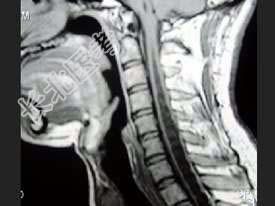

- 单项选择题男,27岁, 常有手、臂的自发性疼痛、麻木、蚁走等感觉异常,结合MRI检查, 最可能的诊断是 ( )

B、脊髓空洞症